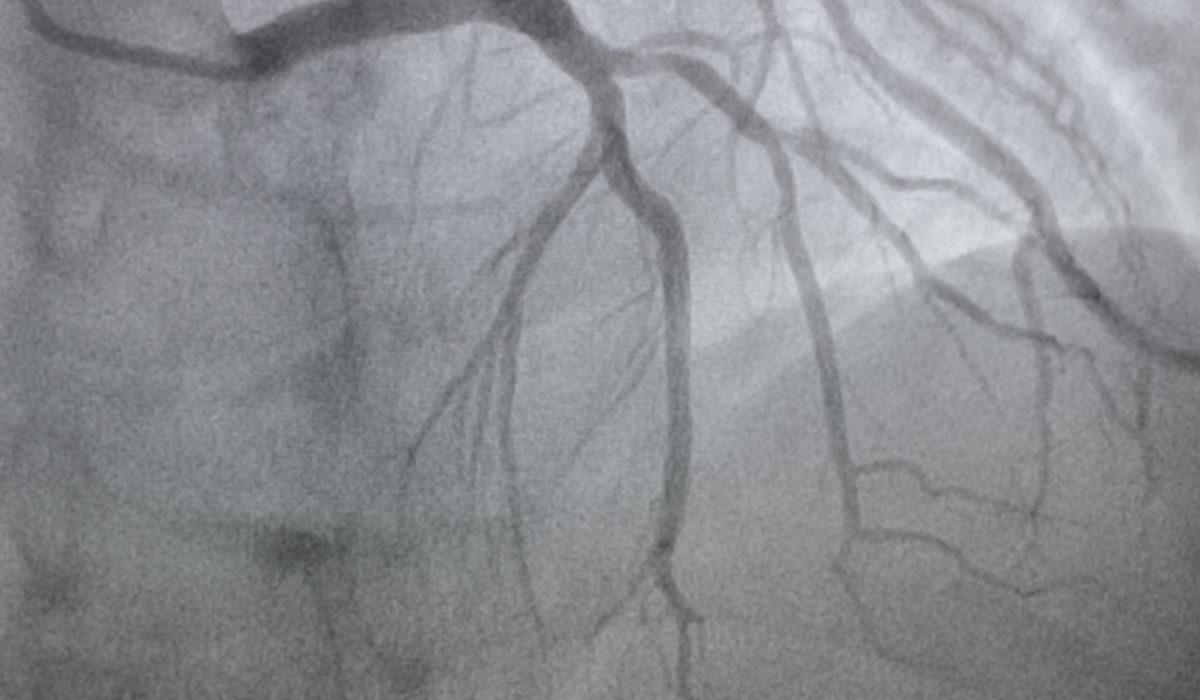

An angiogram is a specialised diagnostic test used to examine the blood vessels of the heart, brain, or other parts of the body. It plays an important role in detecting blockages, narrowing, or abnormalities in arteries and veins. The need for angiograms has increased significantly due to the increasing number of heart disease and blood vessel problems in Bangladesh. Patients often search for the angiogram cost in Bangladesh to plan their treatment effectively. I have listed the cost of angiograms at the top hospitals in Bangladesh.

এনজিওগ্রাম একটি আধুনিক ও নির্ভুল মেডিকেল পরীক্ষা, যার মাধ্যমে হৃদপিণ্ডসহ শরীরের গুরুত্বপূর্ণ রক্তনালীগুলোর ভেতরের অবস্থা সরাসরি দেখা যায়। এই পরীক্ষায় বিশেষ কন্ট্রাস্ট ডাই ব্যবহার করে এক্স-রে প্রযুক্তির মাধ্যমে ধমনীর রক্তপ্রবাহ, ব্লক, সংকোচন বা অন্যান্য অস্বাভাবিকতা শনাক্ত করা হয়। হৃদযন্ত্রের ধমনীর ক্ষেত্রে একে করোনারি এনজিওগ্রাম বলা হয়, যা বুকে ব্যথা, হার্ট অ্যাটাকের ঝুঁকি, শ্বাসকষ্ট বা অস্বস্তির সঠিক কারণ নির্ণয়ে অত্যন্ত গুরুত্বপূর্ণ। এনজিওগ্রামের মাধ্যমে চিকিৎসক ব্লকের পরিমাণ ও অবস্থান নির্ধারণ করে পরবর্তী চিকিৎসা—ওষুধ, স্টেন্ট বা বাইপাস সার্জারি—নেওয়ার সিদ্ধান্ত নিতে পারেন। আধুনিক ক্যাথল্যাব ও অভিজ্ঞ কার্ডিওলজিস্টের তত্ত্বাবধানে এই পরীক্ষা নিরাপদ, দ্রুত এবং জীবনরক্ষাকারী ভূমিকা পালন করে।